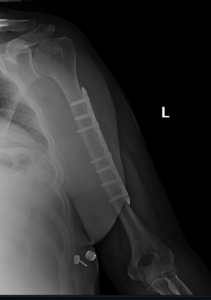

if the fracture is displaced, surgery may be needed to put the bone back into the correct position and fix the bone with Plates & screws or nails for adequate healing to occur.

- Humerus Fractures.